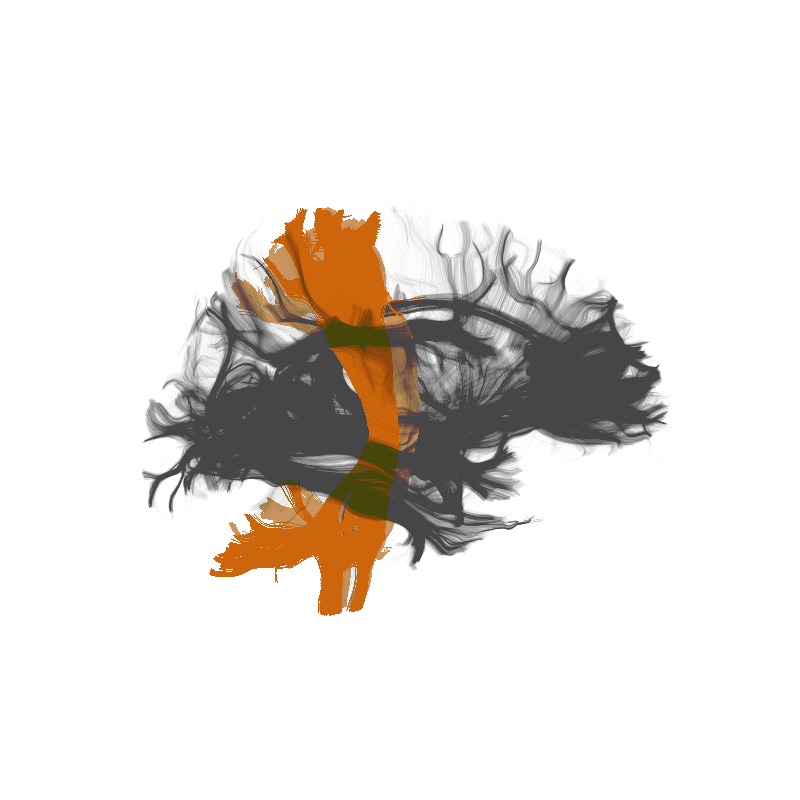

Scaling expertise with citizen science

Anisha Keshavan

Jason Yeatman

https://braindr.us

Multiple ratings per image

Aggregating across raters

XGBoost (Chen & Guestrin, 2016)

Scaling expertise using citizen scientist ratings